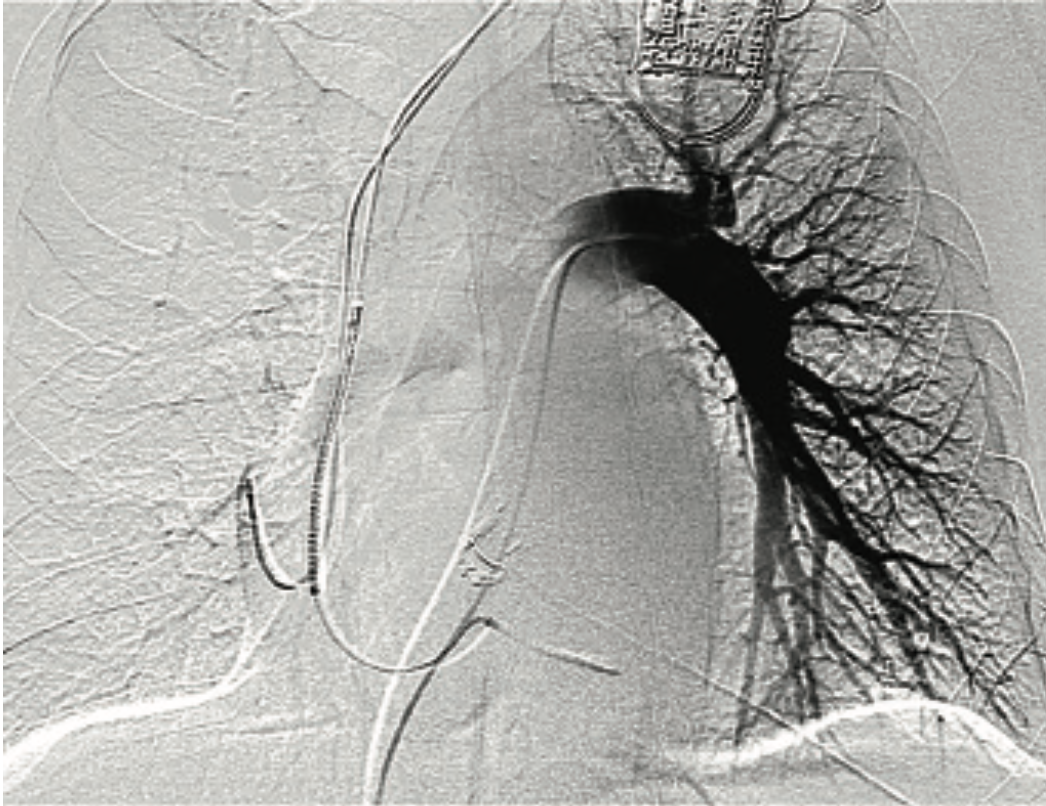

For mitral valve procedures, we use the ACIST to determine the mitral annular plane. It definitely requires high-flow injections, because there is a lot of volume going through the mitral valve. You also have to switch from doing a left atrial angiogram, which requires maybe 10 ccs of contrast, to doing a left ventriculogram, which requires maybe 10-20 ccs of contrast. The ACIST permits us to move between those injections quickly. If you are trying to characterize the left or right atrium in a transseptal procedure, it can easily be done with the ACIST. Another advantage of the ACIST is that because it offers higher and more consistent flow than with a hand injection, I can keep my small catheter in place and still get an optimal result. We also use the ACIST for left atrial appendage closures (Image 1). Using pre-procedural CT scans, the Philips system allows you to overlay your CT images onto the fluoroscopic image. Using an ACIST contrast injection hooked up to the Philips system, you can also do a rotational angiogram to generate a 3D image. We have also used the ACIST for pulmonary angiograms (Images 2-3) and pulmonary stenting. The images show a case of a patient who presented with acute chest pain. We were able to image his coronaries and when these proved to be normal, we performed a pulmonary angiogram in the same setting. For pulmonary valve stenting, you definitely need a contrast injection in the right ventricular outflow tract to make sure you have the necessary size and space. If you do a coarct stent as well, you want a high-flow injection to characterize the anatomy. I was involved in stem cell studies a few years ago, and in determining the sites for injection, we would perform a left ventriculogram to characterize where we want to inject cells, and quickly move to a coronary injection to guide our injections, without having to change the system between angiograms.

This is a 79-year-old woman with emphysema, arthritis, and severe aortic stenosis, and she needed a TAVR. There were several issues with her TAVR: one was that her coronary heights were low. If you put a TAVR valve in a patient with very low coronary heights, there is a chance that the native valve will get pushed up and occlude the coronary artery. We’ve had that happen once before, and the patient died from it, so it is a very serious complication. We did a novel procedure called the bioprosthetic aortic scallop intentional laceration to prevent iatrogenic coronary artery obstruction (BASILICA) procedure, where you slice the leaflet of the native aortic valve in half. Even though the leaflet gets pushed up, since it has been sliced in half, it won’t occlude the coronary artery. We first needed to look at her coronary arteries and the cusps using 3-6 cc coronary injections, and then we performed the BASILICA procedure. The patient also had an anomalous takeoff of her carotid arteries. We wanted to use a carotid embolic protection device, but because she had such an anomalous takeoff, it had to be placed in a very unique way. We did have a CT scan and had to correlate it with the patient so we would know exactly where to put the device. We needed to take an arch angiogram, which is a higher power contrast injection, 10 for 15 ccs or 10 for 20 ccs. The TAVR procedure was done as usual, using the 10 cc contrast injection I described earlier, to measure the annulus planes and look at implant depth. Then we looked at the coronary arteries, because it turned out that the patient needed a stent in her coronary artery. At the end of the case, we wanted to make sure that our closure of the large-bore access sheath was sufficient, so we flipped down to the leg and took a picture there using digital subtraction angiography and a 2 cc injection. I’ll share a second case that also demonstrates the versatility of the ACIST (Images 2-6). This was a patient with acute shortness of breath and chest pain, and there was a question of whether he was having a pulmonary embolus or a heart attack. The electrocardiogram was unclear. We took him back to the lab and were able to do a pulmonary angiogram, then visualize the coronaries, all on one setting. We also did an iliac angiogram, because we used that access in order to give him a support device. This case required pulmonary (Images 2-3), coronary (Images 4-5), and iliac angiograms (Image 6), all done with use of the ACIST CVi system.